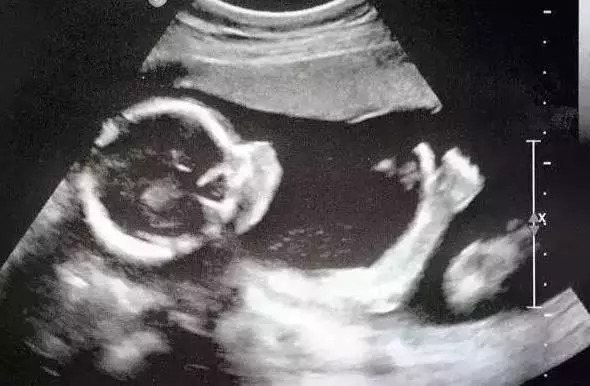

1、胎囊

胎囊是指孕早期(怀孕前三个月)胎儿的胚囊。超声检查中,胎囊一般为圆形或椭圆形,其内可见胚芽(为早期小胚胎),胎囊一般位于子宫腔内。如果B超发现胎囊形状不规则,位置过低(位于子宫腔下部),则可能有发生流产的风险。

2、双顶径、头围、腹围、股骨长

双顶径、头围、腹围、股骨长是B超报告单上最常见的数据。双顶径代表胎头两侧顶骨间的距离,头围是指胎宝宝头的周长,腹围是指腹部的周长,股骨长是指胎宝宝下肢大腿骨的长度,这4个数据都是用来推算胎宝宝大小的指标。

5、胎心

胎心率也称胎心搏动,即是宝宝每分钟胎心跳动的次数。胎心搏动的正常范围是120~160次/分钟。如果B超报告单上出现低于120次/分或高于160次/分、或者心律不齐的情况,则宝宝胎心可能有问题。